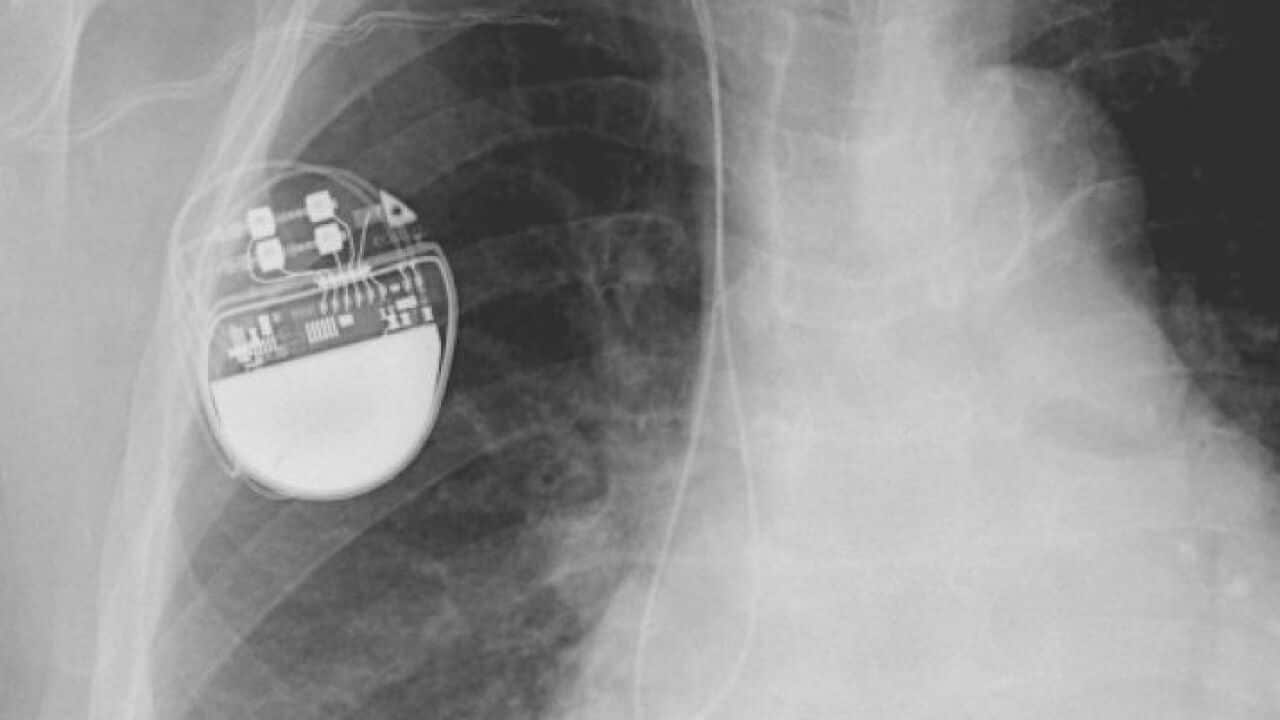

Medtronic makes devices to help control diabetes, manage chronic pain and alleviate Parkinson's disease, and has invented a wireless pacemaker the size of a vitamin pill.